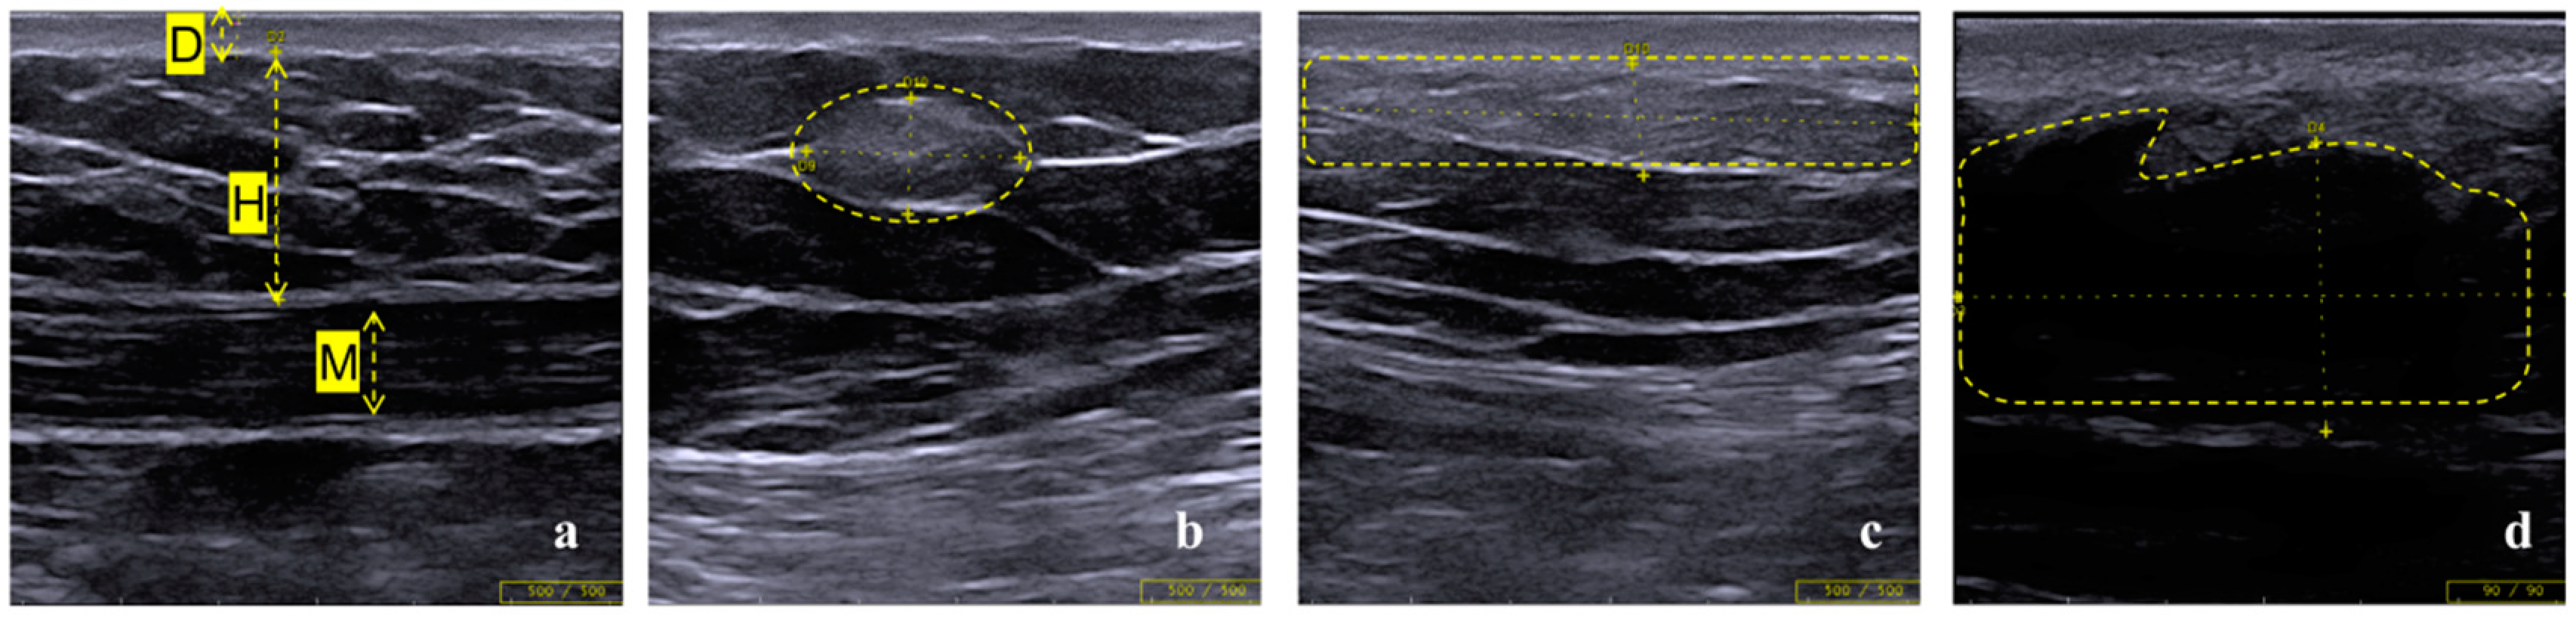

3.3. LH Follow-Up by Ultrasound Assessment

3.4. Hypothesis on the Progression of Insulin Induced Lipohypertrophy